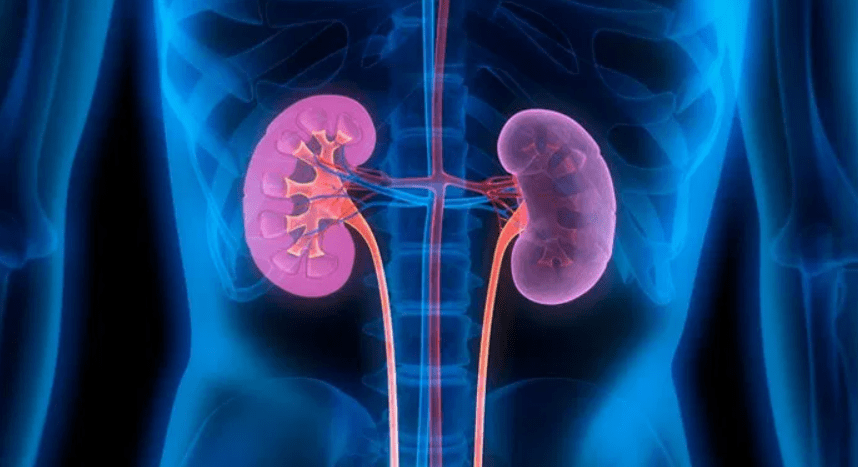

কিডনি রোগ থেকে বাঁচতে মেনে চলুন এই ৯টি নিয়ম !!

আজকাল একটি অন্যতম সমস্যা হলো কিডনির রোগ। নিজের অজান্তেই শরীরের ক্ষতি করতে পারে এই রোগ। হাই ব্লাড প্রেসার, ডায়াবেটিস বা বংশগত রোগের প্রবণতা থাকলেও কিডনিতে একাধিক সমস্যা দেখা যায়। এতে করে মৃত্যুর আশঙ্কা বেড়ে যায়। এ ক্ষেত্রে কিডনি সুস্থ রাখতে কয়েকটি সাধারণ বিষয় মাথায় রাখতে হবে।